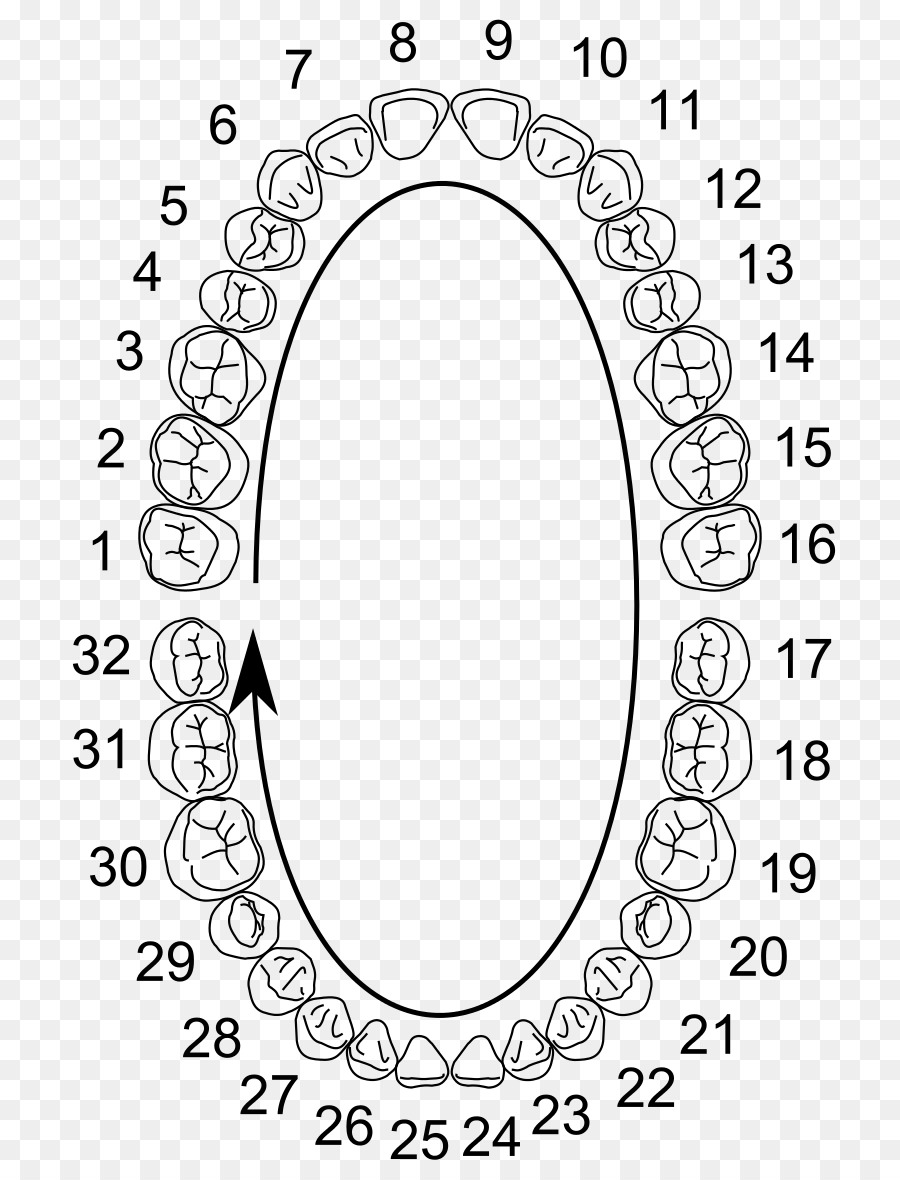

Gigi Geraham Bungsu, Molar, Sistem Penomoran Universal gambar png

Gigi Geraham Bungsu, Molar, Sistem Penomoran Universal gambar png

Buku TA : Susunan Gigi Manusia Dewasa | Evan’s Blog : Kuliah Informatika

Buku TA : Susunan Gigi Manusia Dewasa | Evan’s Blog : Kuliah Informatika

Rumus Gigi Orang Dewasa | Biologi | Sridianti.com

Rumus Gigi Orang Dewasa | Biologi | Sridianti.com